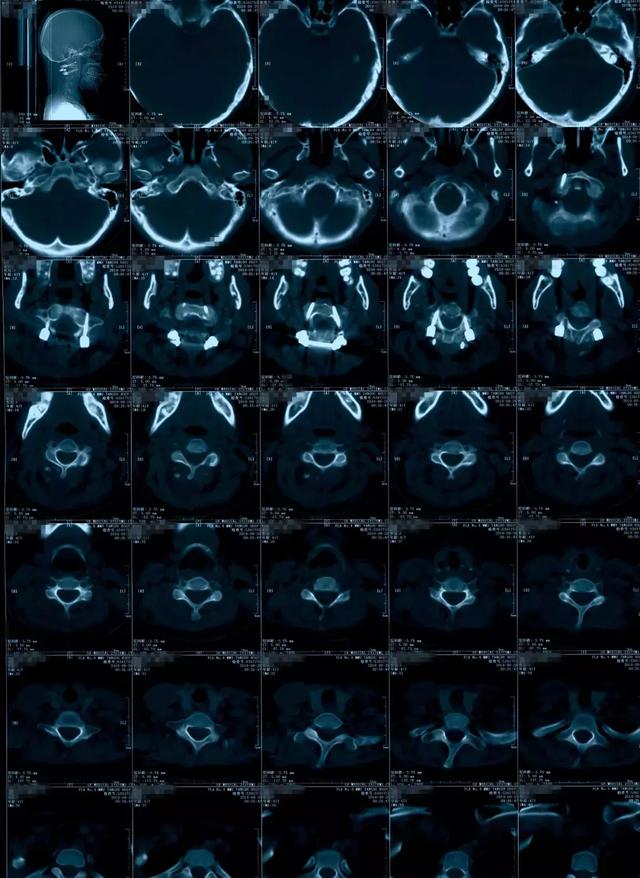

寰枢椎脱位ct

寰枢椎半脱位

寰枢关节脱位的影像诊断

寰枢椎脱位

寰枢关节半脱位的影像学诊断

寰枢椎半脱位(dr)

病例寰枢关节半脱位该如何诊断与治疗

寰枢关节脱位

卧位旋牵法治疗儿童寰枢关节半脱位临床报告1例(现己5例)

病例点评寰枢椎脱位1例

难复性寰枢椎脱位

一例寰枢关节半脱位

一例寰枢关节半脱位的病例报道(转自网络)